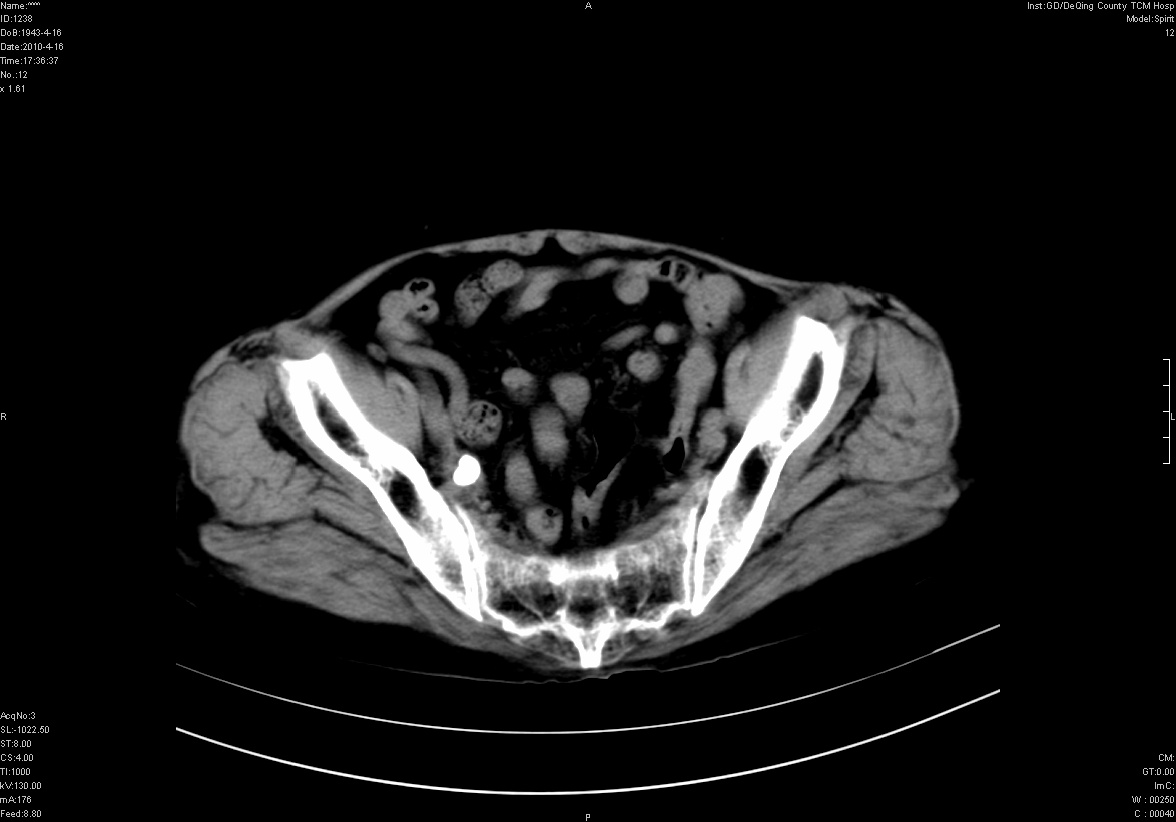

标题: CT25796:女,60岁,腹痛5天,请会诊??? [打印本页]

标题: CT25796:女,60岁,腹痛5天,请会诊???

考虑卵巢畸胎瘤。

支持右侧盆腔畸胎瘤。

畸胎瘤

钙化灶

右侧附件畸胎瘤

考虑右侧卵巢畸胎瘤。

考虑右侧卵巢畸胎瘤

右侧卵巢畸胎瘤可能。